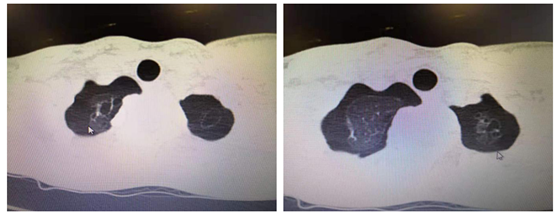

今年在长沙读高三的小林,因10余天前突发左侧胸闷、呼吸困难,在当地医院检查诊断为左侧气胸,经行左侧胸腔闭式引流术后,小林左侧气胸好转,拔管出院。可就在出院两天后,小林却突然又出现右侧胸痛、胸闷,再次入院诊断为右侧自发性气胸,再次置管引流,检查胸部CT发现小林双侧肺尖多发肺大疱。

肺大疱是自发性气胸的病理基础,肺大疱的存在就像身体里装了一个“定时炸弹”,随时都有可能再次发生自发性气胸。对于正处于高三的小林来说,将严重影响小林的学习,这也愁坏了小林一家人。

为了进一步治疗,小林父母慕名赶到湘雅常德医院就诊。由中南大学湘雅医院委派至湘雅常德医院心胸血管外科黄日茂主任考虑到小林正在就读高三的特殊时期,双侧肺大疱分期手术将严重影响到小林的学习。为此,黄日茂主任团队特为小林制定了双侧肺大疱同期手术切除的方案。患者是一位青少年,为了美观,决定为小林行微创单孔胸腔镜肺大疱切除术,只需要在胸壁上切一个2-3cm小口子便能切除小林肺上面的肺大疱。在黄日茂主任、胡邦副主任医师、何志伟医师的共同努力下,小林手术十分成功,术后恢复良好,顺利出院,此时小林父母心头的愁云才舒展开来。